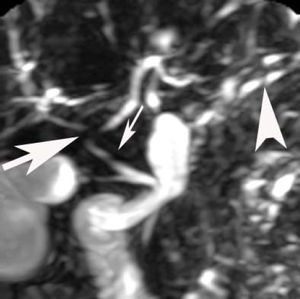

Laparascopically obtained liver biopsy tissue showed bridging fibrosis, nodule formation, portal tract expansion by lymphocytes, plasma cells, and neutrophils, bile ductular proliferation, and periductular fibrosis and edema (Figure 1). Magnetic resonance cholangio-pancreatography revealed beading and narrowing of the intra and extra hepatic bile ducts consistent with sclerosing cholangitis (Figure 2). Because of the short stature and anemia, CD was suspected, and serological evaluation revealed increased IgA antibodies to tissue transglutaminase (385 units; normal, 0-20 units). Histopathological examination of small intestinal biopsies showed total villous atrophy and crypt hyperplasia. The findings were consistent with celiac disease

Our case had advanced severe liver disease, cholangiographic abnormalities suggestive of sclerosing cholangitis, and histological findings of bridging fibrosis and nodule formation. The clinical phenotype of our patient (female child, no inflammatory bowel disease, cholestatic histological features, negative liver autoantibodies, and abnormal findings on magnetic resonance cholangiography) does not allow an easy categorization. The principal diagnostic considerations included primary sclerosing cholangitis (PSC), autoantibody-negative autoimmune hepatitis (AIH), overlap syndrome of PSC and AIH, and CD alone or in concert with PSC or AIH. The diagnostic uncertainty and the severity of the liver disease justified a treatment regimen that addressed all diagnostic considerations, and prednisone, ursodeoxycholic acid and GFD were instituted. The prompt and complete response to this combination regimen within 3 months and the ability to fully discontinue prednisone after 3 months and still maintain normal tests and well-being 4 years later strongly suggested that CD was the principal basis for the liver disease.